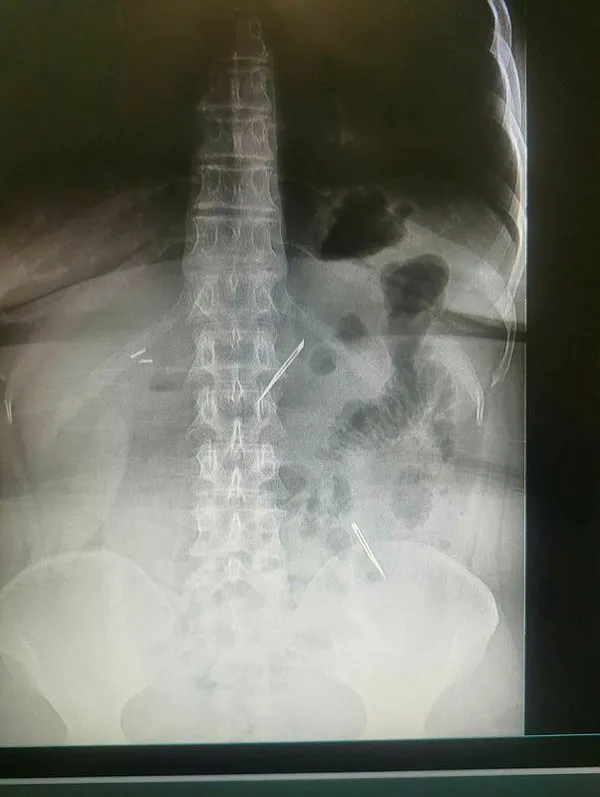

Başkent Ankara'dan ajanslara düşen bu haber büyük bir şaşkınlığa neden oldu. Sağlık Bilimleri Üniversitesi Ankara Atatürk Sanatoryum Eğitim ve Araştırma Hastanesi'ne mide ve karın bölgesinde aşırı ağrı şikayeti ile müracaat eden 46 yaşındaki D.E.'nin yapılan tahlil, tetkik ve çeşitli görüntülemelerden sonra bağırsak kısmında 2 adet neşter olduğu tespit edildi.

Genel cerrahi kliniği tarafından zorlu bir ameliyat sonrasında neşterler kadının vücudundan çıkarıldı. 46 yaşındaki D.E. neşterleri nasıl yuttuğunu bilmediğini tahminen ekmek ile birlikte yutabilmiş olabileceğini ifade etti. Ameliyatı gerçekleştiren Sağlık Bilimleri Üniversitesi Ankara Atatürk Sanatoryum Eğitim ve Araştırma Hastanesi Genel Cerrahi Kliniği Eğitim ve İdari sorumlusu Prof. Dr. Hakan Buluş ise hastanın yoğun şikayetleri üzerine çektikleri röntgen sonrasında 2 adet neşteri görünce şaşkına uğradıklarını söyledi.

Hastanın şikayetlerinin artması üzerine gerçekleştirilen tetkiklerde 46 yaşındaki kadının karın bölgesinde 2 adet yabancı cisim olduğunu tespit ettiklerini, detaylı inceleme sonucunda bu cisimlerin neşter olduğunu fark ettiklerini belirten Prof. Dr. Buluş, "Yaklaşık 10 gün önce kliniğimize karın ağrısı ve bulantı şikayetleri ile başvurdu. Bizim yaptığımız fiziki muayene ve tetkiklerinde hastanın direkt karın grafisinde 2 adet yabancı cisim olduğunu tespit ettik. Aslında yabancı cisim bizim güncel grafiğimizde sık karşılaştığımız bir durum değil, fakat nadir de olsa görebildiğimiz bir patoloji. Biz de bunun üzerine ayrıntılı değerlendirmeler ve tetkikler yaptık. Sonrasında 2 adet yabancı cismin bistüri (neşter) ile uyumlu olduğunu gördük. Bunun üzerine hastanın şikayetlerinin de artması üzerine, ameliyat kararı verdik. Yaptığımız ameliyatta ince bağırsağın yaklaşık 180'inci santimetresinde bu yabancı cisimlerin olduğunu tespit ettik. Bunun üzerine ameliyatla bunları çıkarttık. Hastamızın sağlık durumu şuan gayet iyi. Ameliyattan sonraki üçüncü günü. Şuan bir problemi yok, inşallah birkaç gün içerisinde şifa ile taburcu etmeyi düşünüyoruz" şeklinde konuştu.

Çıkardıkları cismin, neşterin normalde ameliyatlarda kullanılan bir malzeme olduğunu söyleyen Prof. Dr. Buluş, "Çıkardığımız yabancı cisimler bizim ameliyatlarda sıkça kullandığımız 11 numara dediğimiz bir bistüri tipi. Ebatları da yaklaşık 4 santime yarım santim ebatlarında. Ucunun sivri olması nedeniyle ince bağırsak mukozasına saplanarak enflamasyon ve bir karın ağrısı yapması, sonrasında da ağrı şikayetlerinin artmasına neden olmasından dolayı ameliyat kararı verdik" diye konuştu.